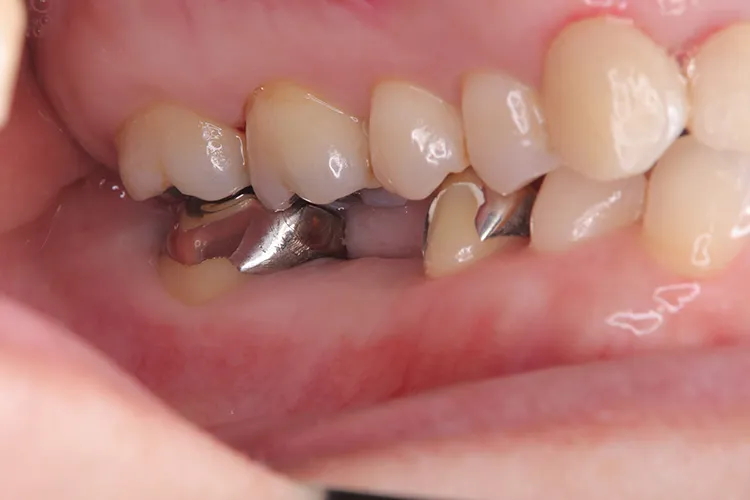

症例2/

臼歯1本

- 治療期間

- 3ヶ月

- 費用

- 51万円(税込)

治療前

治療後

レントゲン画像

治療内容

第一大臼歯1歯欠損をインプラントで回復したケースです。第一大臼歯は永久歯の中で一番最初に生える歯ですが、一番早く傷んでしまう歯でもあります。噛む力の60%を負担し噛み合わせの安定に大きく影響しますので、この歯が欠損すると噛み合わせに悪い影響を与えてしまいます。インプラントで治すことにより噛み合わせが安定するだけでなく、ブリッジのように隣在歯を削らないので天然歯の寿命を延ばすメリットもあります。